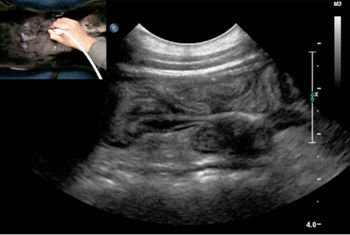

You don't have an ultrasound machine in your practice yet, but you're thinking that it might be ideal for that case that just walked into your door. Here's one imaging expert's guidance on which cases are mostly likely to yield diagnostic results.